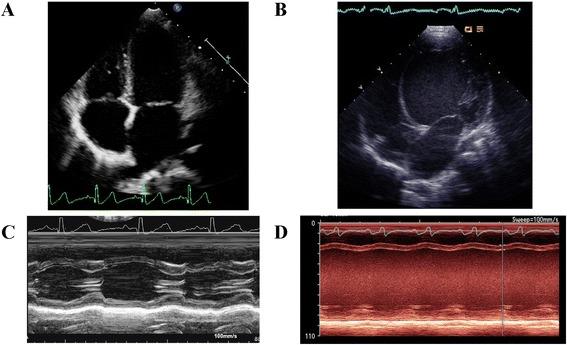

In this study we identified a novel variant R205Q in the cardiac troponin T gene (TNNT2). Carriers of the variant allele exhibited increased chamber volumes associated with decreased left ventricular ejection fraction. To clarify the causal role of this variant, we generated recombinant variant human protein and examined its calcium kinetics as well as the maximally activated ADP release of human β-cardiac myosin with regulated thin filaments containing the mutant troponin T. We found that the R205Q mutation significantly decreased the calcium sensitivity of the thin filament by altering the effective calcium dissociation kinetics.

在这项研究中,我们在心肌肌钙蛋白 T 基因(TNNT2)中发现了一个新的变异 R205Q。携带变异等位基因的个体表现出心室容积增加,同时伴有左心室射血分数降低。为了阐明该变异的因果作用,我们生成了重组变异的人类蛋白,并研究了其钙动力学以及含有突变肌钙蛋白 T 的调节薄丝的人类β-心肌球蛋白的最大激活 ADP 释放。我们发现 R205Q 突变通过改变有效钙离解动力学显著降低了薄丝的钙敏感性。